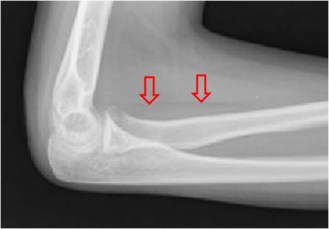

SIGNO DE LA BANDA DEL ESCAFOIDES

La banda adiposa del escafoides es una imagen lineal o triangular de densidad grasa, que se localiza entre el escafoides y las vainas tendinosas del abductor largo y del extensor corto del pulgar. El borramiento o desplazamiento de esta línea se presenta en las fracturas del escafoides, de la apófisis estiloides radial o de la base del primer metacarpiano, aun cuando no se vea la línea de fractura. En el ejemplo puede verse el borramiento de la banda adiposa del escafoides y la fractura de este hueso.

La flecha marca la banda adiposa del escafoides en una radiografía normal.